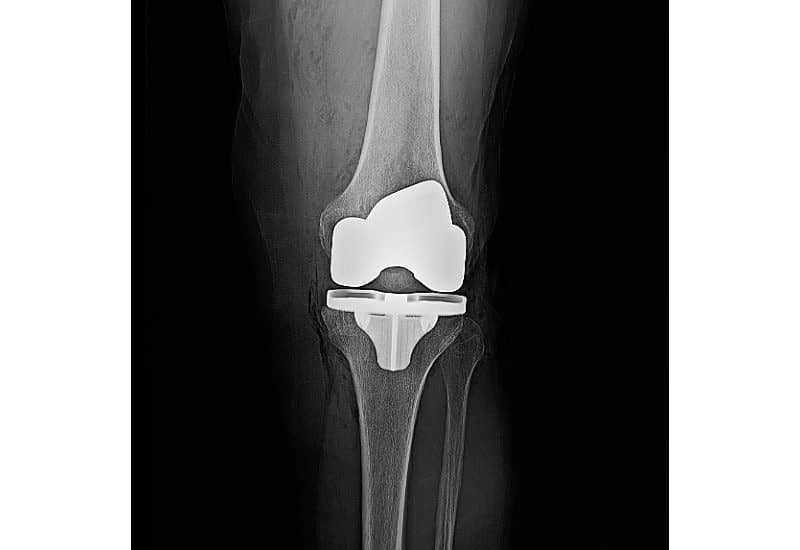

Magnetic resonance (mr) imaging allows for comprehensive imaging evaluation of the tissues surrounding knee arthroplasty implants with metallic components, including the polyethylene components. Optimized conventional and advanced pulse sequences can result in substantial metallic artifact reduction and afford improved visualization of bone. On the other hand, preserved. If a soft tissue abnormality is. In partial knee replacement such as patellofemoral replacement (pfr) or unicondylar knee replacement (ukr), the metallic burden for imaging is lower. Mri is safe in patients with orthopedic implants regarding migration and torque. Additionally, ct can also help evaluate whether the parts of the joint replacement have rotated from the initial placement.